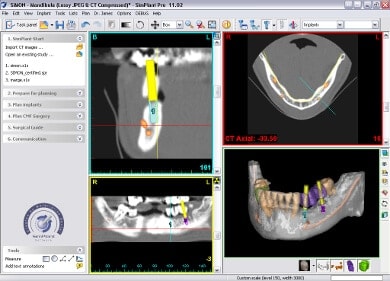

Herzstück des All-on-4 / 6 – Behandlungskonzepts mit Camfour™ ist die aufwendige 3D-basierte Diagnostik. Diese findet im Vorfeld der eigentlichen Zahnimplantation statt. Mit Hilfe von dreidimensionalen DVT-Röntgenaufnahmen und der hochmodernen SIMPLANT®-Software macht sich unser Experte für Implantologie, Dr. Mintert ein detailgenaues Bild von Ihrem Kiefer. Dabei interessieren ihn nicht nur das verfügbare Knochenvolumen, sondern auch die empfindlichen Strukturen des Kiefers, die Knochenqualität und der umliegenden Bereiche. Hierzu gehört neben der Kieferhöhle auch Ihr Unterkiefernerv, auf den wir beim Implantationsvorgang besonders achtgeben müssen. Mithilfe der 3D-Diagnostik kann der Zahnarzt auch feststellen, ob All-on-four/six überhaupt für Sie geeignet ist.

Unter Einsatz der SIMPLANT® Planungssoftware kann der Implantolgoe die optimalen Implantatpositionen vorab am Computer planen, wobei sämtliche Planungsdaten anschließend in die Herstellung einer individuellen Bohrschablone einfließen. Die Bohrschablone ermöglicht ein punktgenaues, schonendes Einsetzen der Implantate an den zuvor geplanten Positionen, minimiert das Verletzungsrisiko und beschleunigt letztendlich die Heilung.